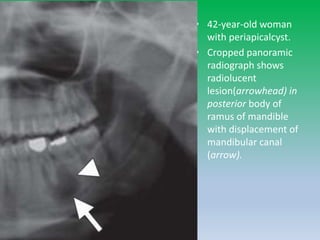

• 42-year-old woman

with periapicalcyst.

• Cropped panoramic

radiograph shows

radiolucent

lesion(arrowhead) in

posterior body of

ramus of mandible

with displacement of

mandibular canal

(arrow).